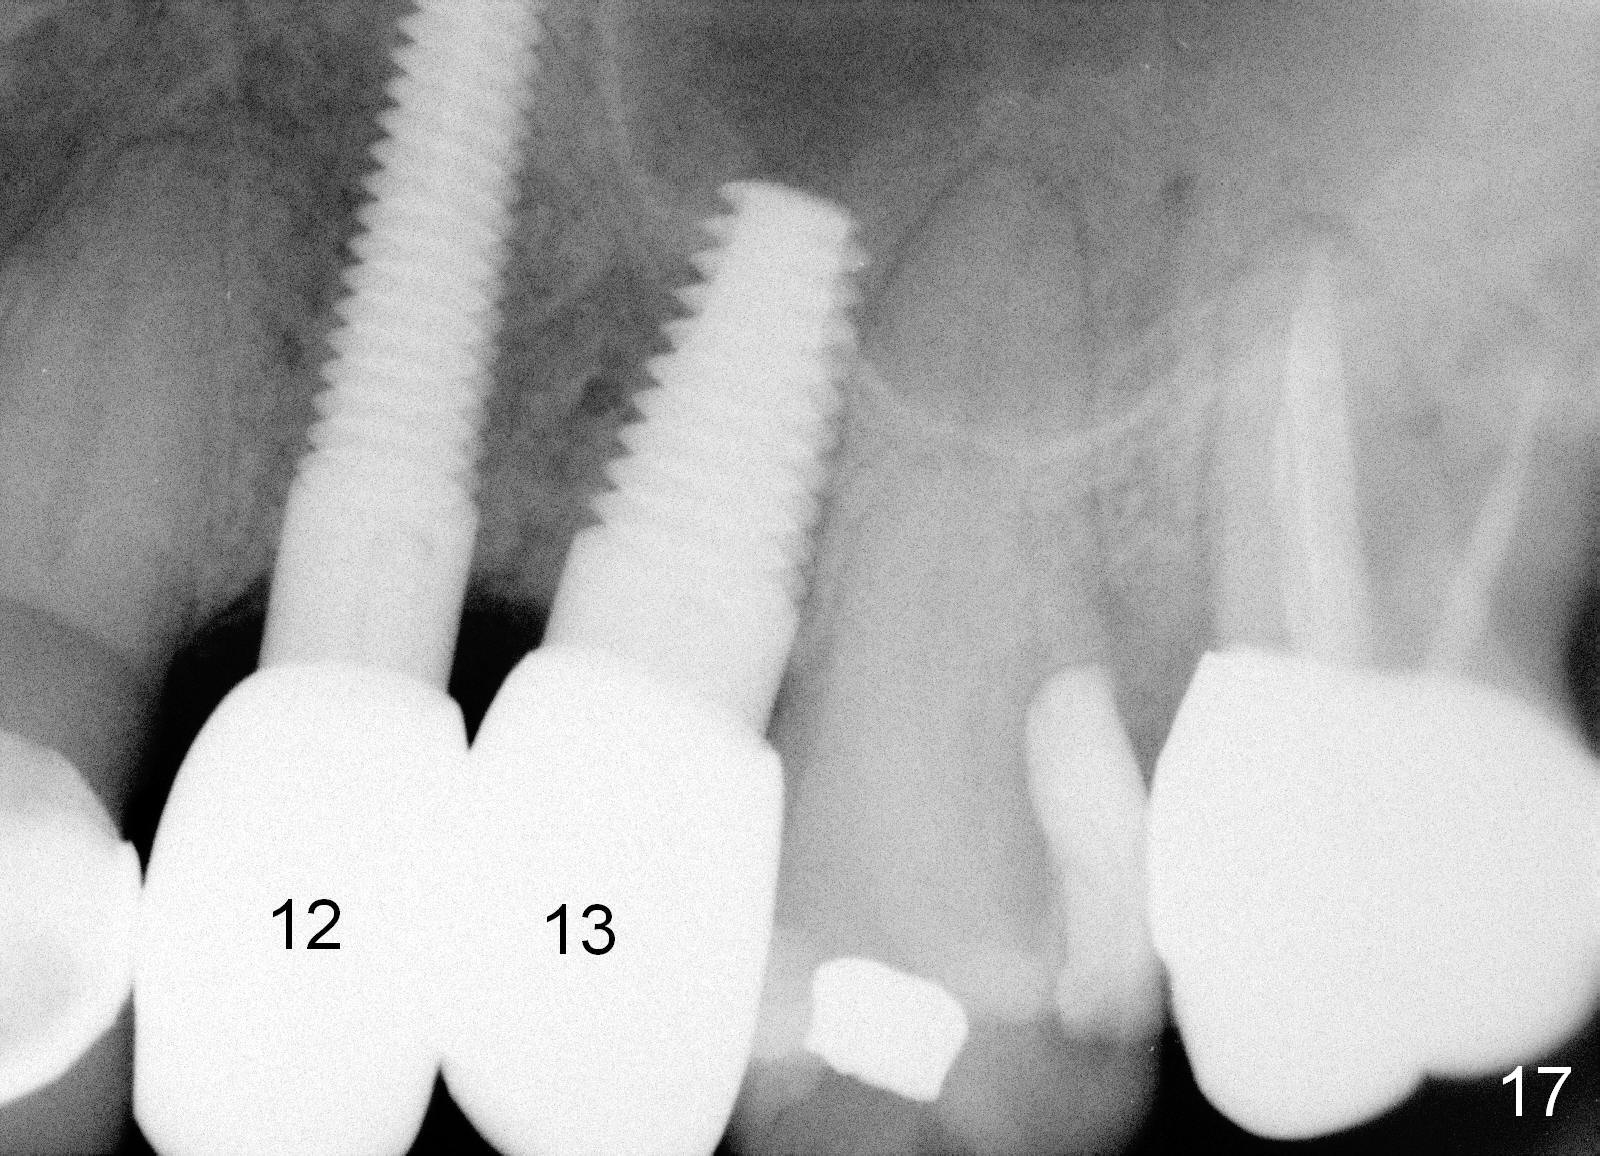

The anterior retainer is kept as a crown at #11 (Fig.2: C), whereas the residual root at the site of #13 is extracted with apical perforation (Fig.3 ^). It is confirmed by Fig.4 (<). To close the perforation, an osteotomy is initiated on the palatal wall of the socket with a 2 mm osteotome (Fig.5 insert: circle). As the osteotomy is being enlarged by a 3 mm osteotome, the bone between the original socket and the osteotomy is being pushed buccally. The former is being closed (Fig.5). The osteotomy is finished with combination of osteotomes and reamers. Fig.6 shows that a 5x14 mm tap is inserted at the site of #13 and that the sinus floor is lifted. In fact the sinus membrane is partially torn at the osteotomy, which is repaired by insertion of Colla-form Dressing (Impladent), followed by autogenous bone (harvested from reamers) mixed with Osteogen (Impladent). A 5x14 mm implant is placed at the site of #13 with insertion torque more than 60 Ncm (Fig.7: I). An incision is made at the site of #12 to start osteotomy with insertion of a parallel pin (Fig.7 P). A 3 mm reamer is kept in place for position confirmation (Fig.8 R). Due to ridge atrophy (Fig.2 arrowheads), a much smaller, but longer implant is placed at the site of #12 (Fig.9: 4x17 mm). The autogenous bone harvested from #12 osteotomy is placed in the buccal gap of #13, followed by insertion of Colla-form Dressing (Fig.10 M). To protect the membrane, a short abutment (4x3 mm) is temporarily placed (Fig.9,10 A) and perio dressing (Fig.9 D) is applied around the abutment and the interproximal areas of the neighboring teeth. Usually perio dressing dislodges around 1 week postop, particularly for a large edentulous space. In this case, the dressing is quite stable 11 days postop: the abutment (Fig.11 A) appears to contribute to retention of the dressing (D).

Three month follow-up shows that the gingiva and bone heal around these two implants (Fig.13-15). Crowns are cemented 4.5 months postop (Fig.16). There is no or minimal bone loss 9 months post cementation (Fig.17, as compared to Fig.15). The bone is stable around the implants 18 months post cementation (Fig.18 panoramus). Root canal therapy is done at #14 between the last follow up appointments.